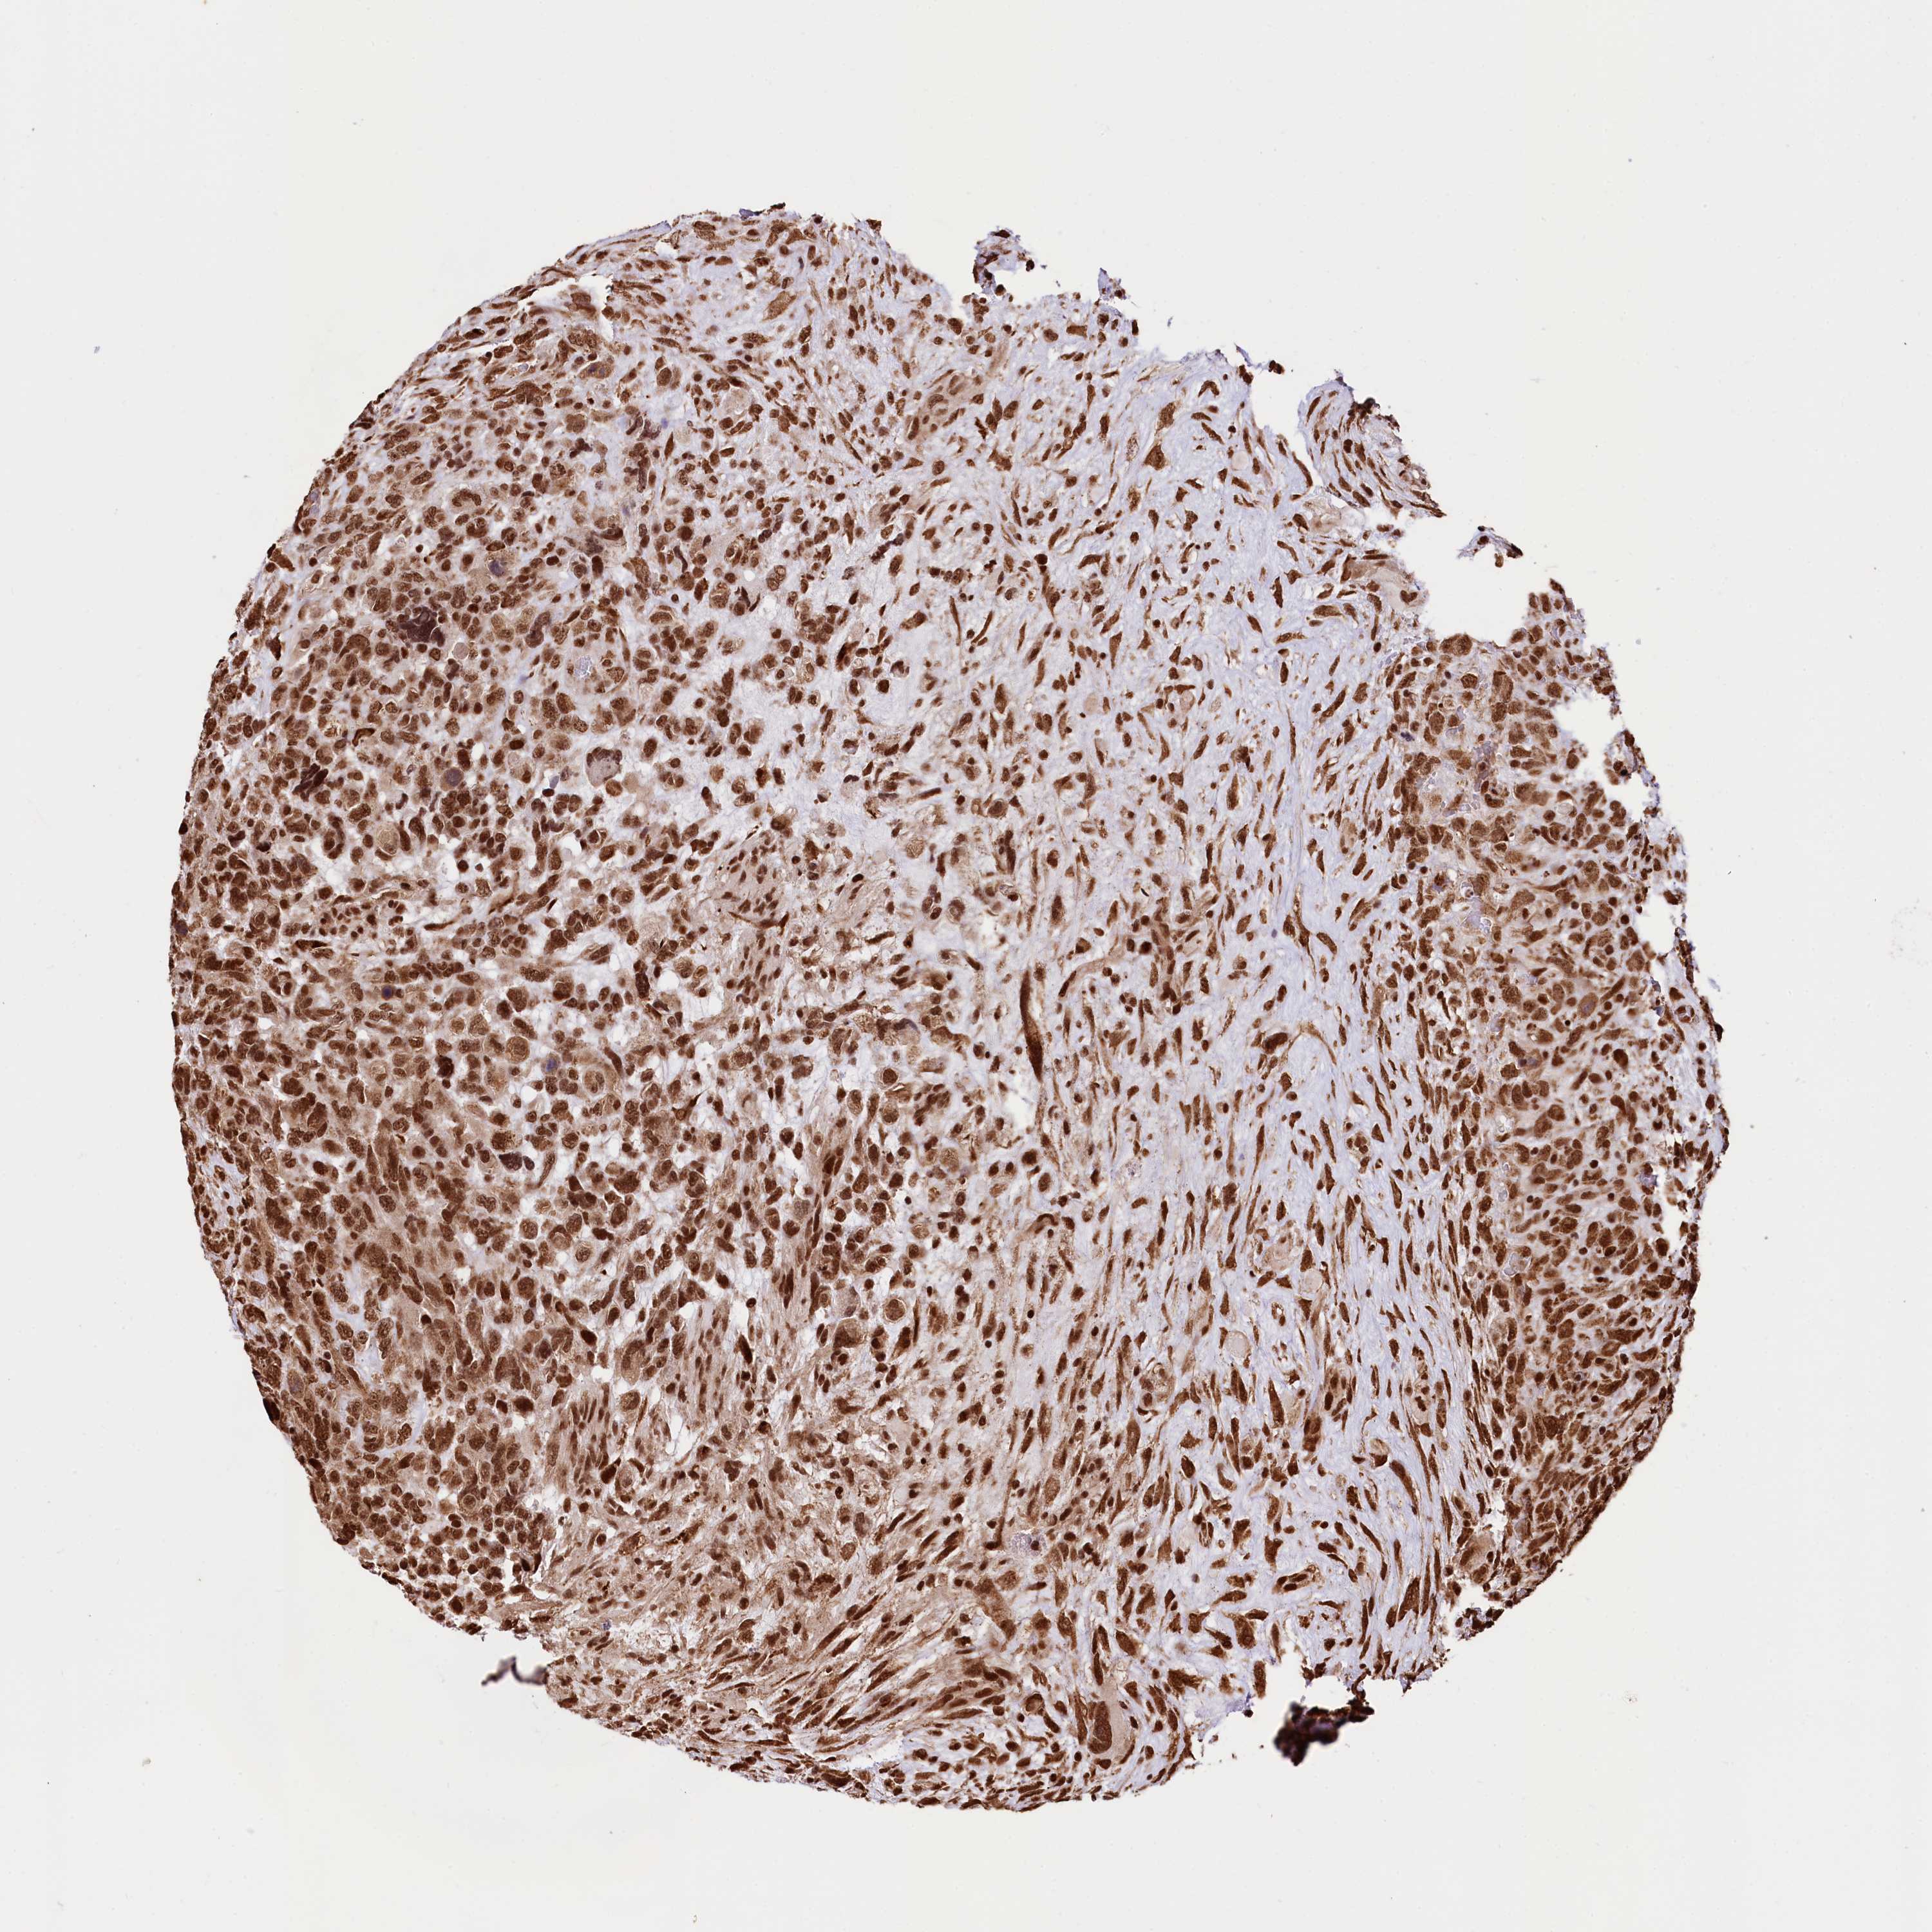

GLIOMA - Protein expressioni

A mouse-over function shows sample information and annotation data. Click on an image to view it in a full screen mode. Samples can be filtered based on level of antibody staining by selecting one or several of the following categories: high, medium, low and not detected. The assay and annotation is described here.

Note that samples used for immunohistochemistry by the Human Protein Atlas do not correspond to samples in the TCGA dataset.

Antibody stainingi

Antibody staining in the annotated cell types in the current human tissue is reported as not detected, low, medium, or high, based on conventional immunohistochemistry profiling in selected tissues. This score is based on the combination of the staining intensity and fraction of stained cells.

Each image is clickable and will lead to virtual microscopy that enables deeper exploration of all samples and also displays staining intensity scores, fraction scores and subcellular localization as well as patient and tissue information for each sample.

Antibody HPA039513

Antibody HPA040015

Staining

High

Medium

Low

Not detected

Intensity

Strong

Moderate

Weak

Negative

Quantity

>75%

75%-25%

<25%

None

Location

Nuclear

Cytoplasmic/membranous

Cytoplasmic/membranous,nuclear

Glioma, malignant, High grade

Glioma, malignant, Low grade